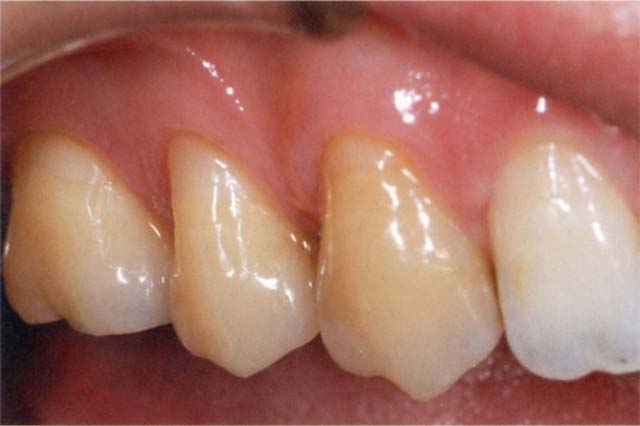

高い審美性を持つフロアブルレジンであれば、第一の適応は楔状欠損であろう。その理由として、従来フロアブルレジンはフレキシビリティが高く、歯頸部のように応力がかかる部位に有効である点が挙げられる。スマイル時に前歯部だけでなく上・下顎の第一・第二小臼歯の歯頸部まで見える人が多いが、そのような患者さんで審美面の要求が高い場合でも、十分対応できる。

その他にも、エナメル質の剥離や変色した部分のコーティング、V級窩洞や臼歯部の咬合圧のかからない小さめの窩洞、MI治療全般などが挙げられる。